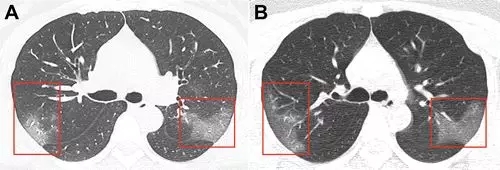

病例1,33岁女性,在武汉工作,

今年1月份回到兰州后

第二天开始发热,咳嗽,

5天后,她去医院检查,

她咽喉部分泌物中发现新冠病毒核酸,

肺部CT扫描(见下图A)

两侧肺上叶肺段呈斑片状毛玻璃样显影。

医生给她用了很多药物,

甚至用上了干扰素,

3天后,再次CT检查发现,

两肺的毛玻璃显影更大了(图片B),

显示治疗效果不好,病情加重。

图片来自《Radiology》杂志